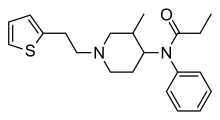

Anilidopiperidines